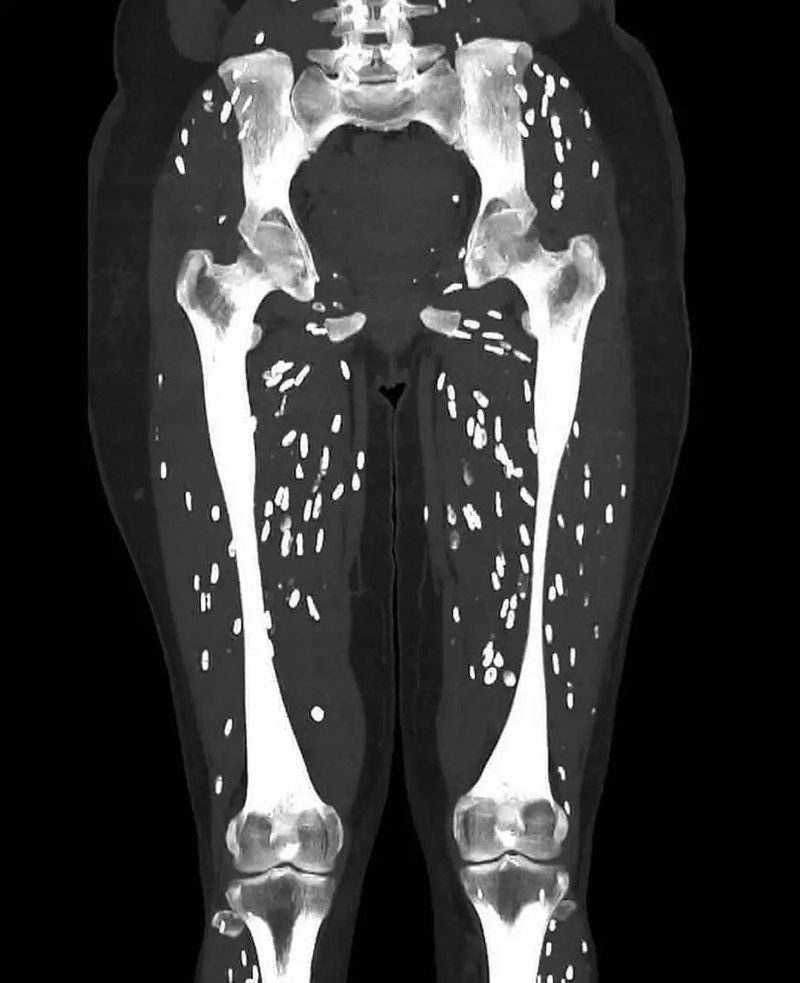

Dr Sam Galley, yang bekerja di University of Florida Health Jacksonville, menunjukkan hasil CT scan kaki pasien yang penuh dengan infeksi parasit di otot.

Munculnya cacing pita pada kaki penderita yang makan daging babi kurang matang. Foto: X/ Sam Galli, M, D |

Menurut Dr. Galli, infeksi tersebut muncul pada CT scan sebagai bintik putih yang umumnya dikenal sebagai 'kalsifikasi butiran beras'. Setelah 5-12 minggu, kista yang membengkak bisa berubah menjadi mengecil, tambahnya.